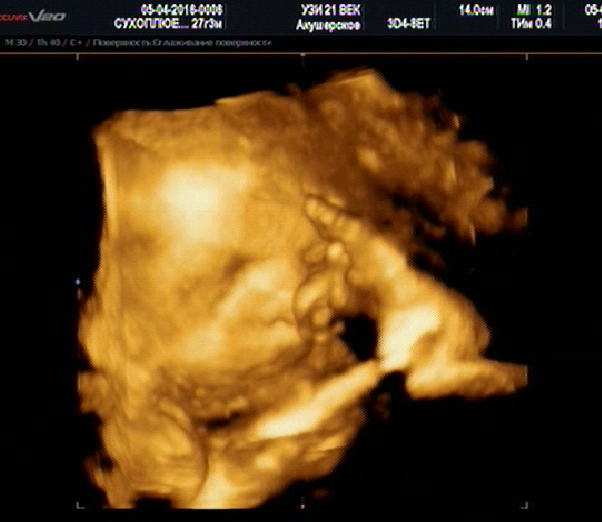

моя пуговка) 30 недель, предположительный вес 1500гр. пдр 11 06

@ulyana482 узи 21 век, на комендантском, у Зимина. 2800+ 400 р диск и фото

Прелесть 😍А где УЗИ Делали ???и сколько стоит ?